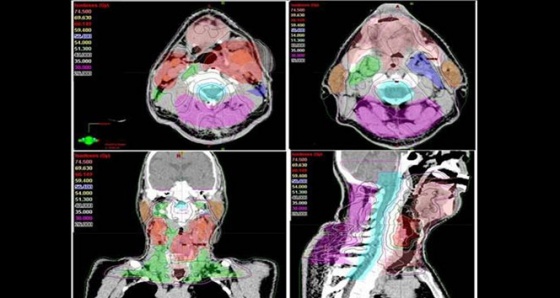

Antalya’da kanser kliniği uzmanlarından Radyasyon Onkolojisi Prof. Dr. Ali Aydın Yavuz, kanser hastalarının radyoterapisi sırasında ‘Yapay Zeka’ uygulamalarının kanserde tedavi başarısını arttırdığını belirtti. Son yıllarda yapay zeka uygulamalarının kanser alanında kullanılmasına yönelik araştırmalarda artış olduğunu ifade eden Prof. Dr. Yavuz, “Tümör ve çevredeki normal dokuların üç boyutlu olarak sınırlarının çizildiği bu süreç, bir hastanın tümör bölgesine ne kadar radyasyon alacağını ve ışının en uygun nasıl odaklanacağını belirler. Özellikle ABD’nin Ulusal Sağlık Enstitüsünce desteklenen önemli bir araştırma projesinde "Yapay Zeka’ kullanarak yüksek riskli tümör hedef hacimlerinin sınırlarının 3 boyutlu olarak belirlenmesi için her bir görüntüleme film kesitinde tümör ve normal doku sınırlarının tek tek çizilmesi (konturlama) işlemlerini otomatikleştirmek için yeni bir yöntem geliştirildi” dedi.

Bu çalışmanın sadece yüksek riskli tümör hacimlerinin ’Yapay Zeka’ ile otomatik bir şekilde ve çok yüksek doğrulukta belirlenmesine yönelik olduğunu dile getiren Prof. Dr. Yavuz, "Bir sonraki aşamada, eldeki tüm veriler birleştirilerek, orta ve düşük riskli tümör bölgelerinin de otomatik ve en doğru bir şekilde belirlenmesi mümkün olabileceği gibi, hastaya özgü en uygun radyoterapi veya kemoterapiyi de ayarlamak adına çeşitli genetik mutasyonlara ait bilgiler de bu yapay zeka uygulamasına entegre edilebilecektir. Bu şekilde, kanser tedavisi sonuçlarında başarı oranlarının artması da kaçınılmazdır. Yöntemin çok önemli bir avantajı da bizlere sunduğu yüksek hız ve verimliliktir. Normalde, örneğin bir baş boyun kanserinde, hedeflenen hacimleri belirlemek bir hekimin 1-4 saatini alır. Yapay Zeka kullanan özel bilgisayar sistemi ile hem bir dakikadan kısa bir sürede hedef hacimler belirlenebilmekte, hem de hekimden hekime değişebilen hata payları ihtimali tümüyle ortadan kalkmaktadır. Bu yöntem, özellikle, hedef hacim belirleme alanında tecrübeli uzman sayısının daha az olduğu düşük ve orta gelir düzeyindeki ülkelerde çok büyük bir kolaylık sağlayacaktır, ancak bu yöntemin ABD gibi gelişmiş ülkelerde de kanser tedavilerindeki yararlılık ve verimliliği çok artıracağı açıktır" şeklinde konuştu.